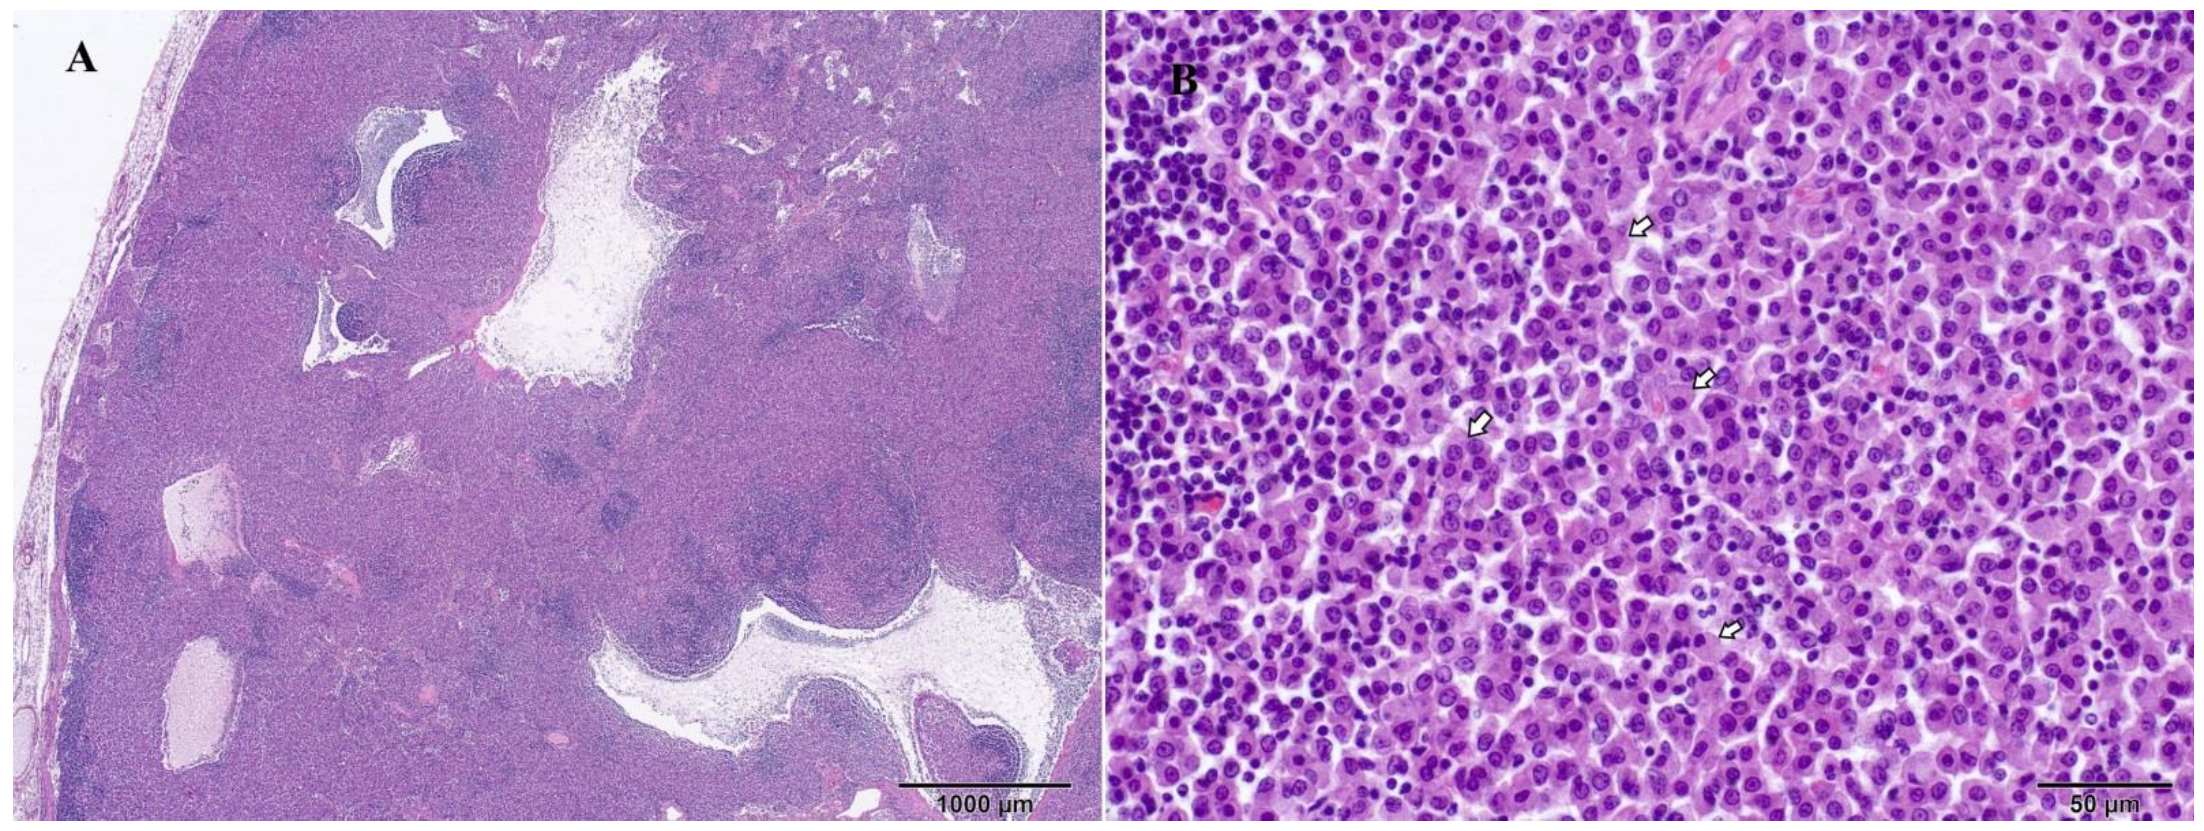

3.4. Histopathological Findings